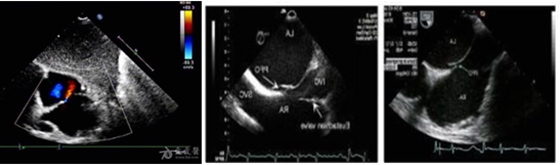

卵圆孔未闭超声图

今年李阿姨健康体检时行心脏彩超检查发现:心脏卵圆孔未闭。难道李阿姨的头痛会与这个问题有关吗?

卵圆孔未闭是一种先天性心脏结构异常。卵圆孔是心脏房间隔胚胎时期的一个生理性通道,正常情况下婴儿出生后2个月左右融合,若超过1岁未能融合则形成卵圆孔未闭。当各种原因(如剧烈运动、咳嗽、潜水等)导致患者右心房压力超过左心房压力时,卵圆孔未闭可致心脏内血流出现明显的右向左异常分流。从而引起不明原因的脑卒中、偏头痛、减压病、斜卧呼吸-直立性低氧血症等相关临床综合征,开始出现相应症状,包括不明原因的的头痛、头晕、呼吸困难或肢体无力。